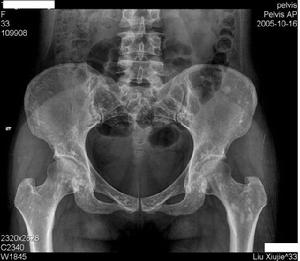

骨斑點症是一種以骨內多發硬化斑點為特點,多為散發。文獻報導有遺傳性及家族性,極為罕見。家族性發病者為常染色體顯性遺傳,患者雙親中必有一位為患者。據統計不足人群中的1/1000萬。本病病因尚未明了,可見於任何年齡階段,遺傳與性別無關。本報告病例,有明顯遺傳性。對其直系親屬進行檢查,發現患者父親及奶奶骨盆X線與患者相類似,患者母親無相關病變。診斷

脆弱性骨硬化病史追查:檢查患者父母及爺爺奶奶。X線透視下見雙上肢、雙肩、脊柱、雙下肢骨質無明顯異常。患者父親及奶奶骨盆X線檢查可見骶骨、髂骨、股骨上段多發性分布不均,大小不等,密度增高的圓形斑點狀緻密影,邊緣清晰,大小約0.3cm2,與患者相似。